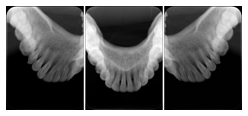

2 Occlusal Vertical Maxilla A Dental Image Layout

DL-C001A

Reference: DL-C001-U1L0

Reference: DL-C001-U2L0